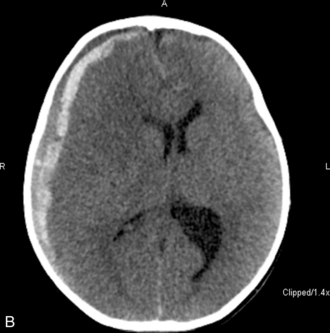

The patient with an acute SDH may demonstrate bilateral hematomas and evidence of diffuse neurologic injury. Because acute subdural hematomas are associated with underlying parenchymal injury, they are generally considered more lethal than EDHs. Approximately two thirds of all children with SDHs lose consciousness immediately after the cranial trauma. Frequently, the child demonstrates focal signs of injury, such as unilateral pupil dilation, focal seizures, or hemiparesis. Because most of these patients sustain additional cerebral injuries, including cerebral lacerations, contusions, and intracerebral hematomas, intracranial hypertension can develop rapidly and progress to severe levels.

Diagnosis of an acute or chronic SDH can be confirmed with a CT scan or angiography. The acute SDH is a crescent-shaped mass, and edema is usually present. The SDH is usually more diffuse than an EDH, the borders are less sharp, and the EDH may be less isodense because the blood mixes with CSF. Radiographic studies are extremely important because they can help determine the need for surgery.50

The patient with an SAH may experience a sudden onset of a severe headache (the most common symptom and present in nearly all cases), emesis, syncope, meningismus, and photophobia. These symptoms are associated with a rapid rise in ICP. Left untreated, the child will progress to coma and possibly death. Although spontaneous SAHs can arise from a variety of sources, including aneurysms, coagulation disorders, and small artery ruptures, trauma remains the leading cause of an SAH in children. CT scans performed within 48   hours of a hemorrhage will detect the vast majority of subarachnoid hemorrhages. The blood will appear as a white, hyperdense area in the subarachnoid spaces (see Fig. 11–12, B and C).

Throughout the child's care, the nurse must be alert for signs of increased ICP (see Increased Intracranial Pressure). The sudden appearance of irritability, confusion, lethargy, and pupil dilation must be reported to a physician or other on-call provider immediately. Emergency acute management of sudden increases in ICP requires immediate intervention with support of the airway, oxygenation, and ventilation and administration of mannitol (0.5-1   gm/kg IV) or 3% saline (3-5   mL/kg IV bolus), or both. A CT scan is typically performed to detect any mass lesion requiring surgical intervention; the CT scan also will enable the evaluation of cerebral edema (see Fig. 11-12).20